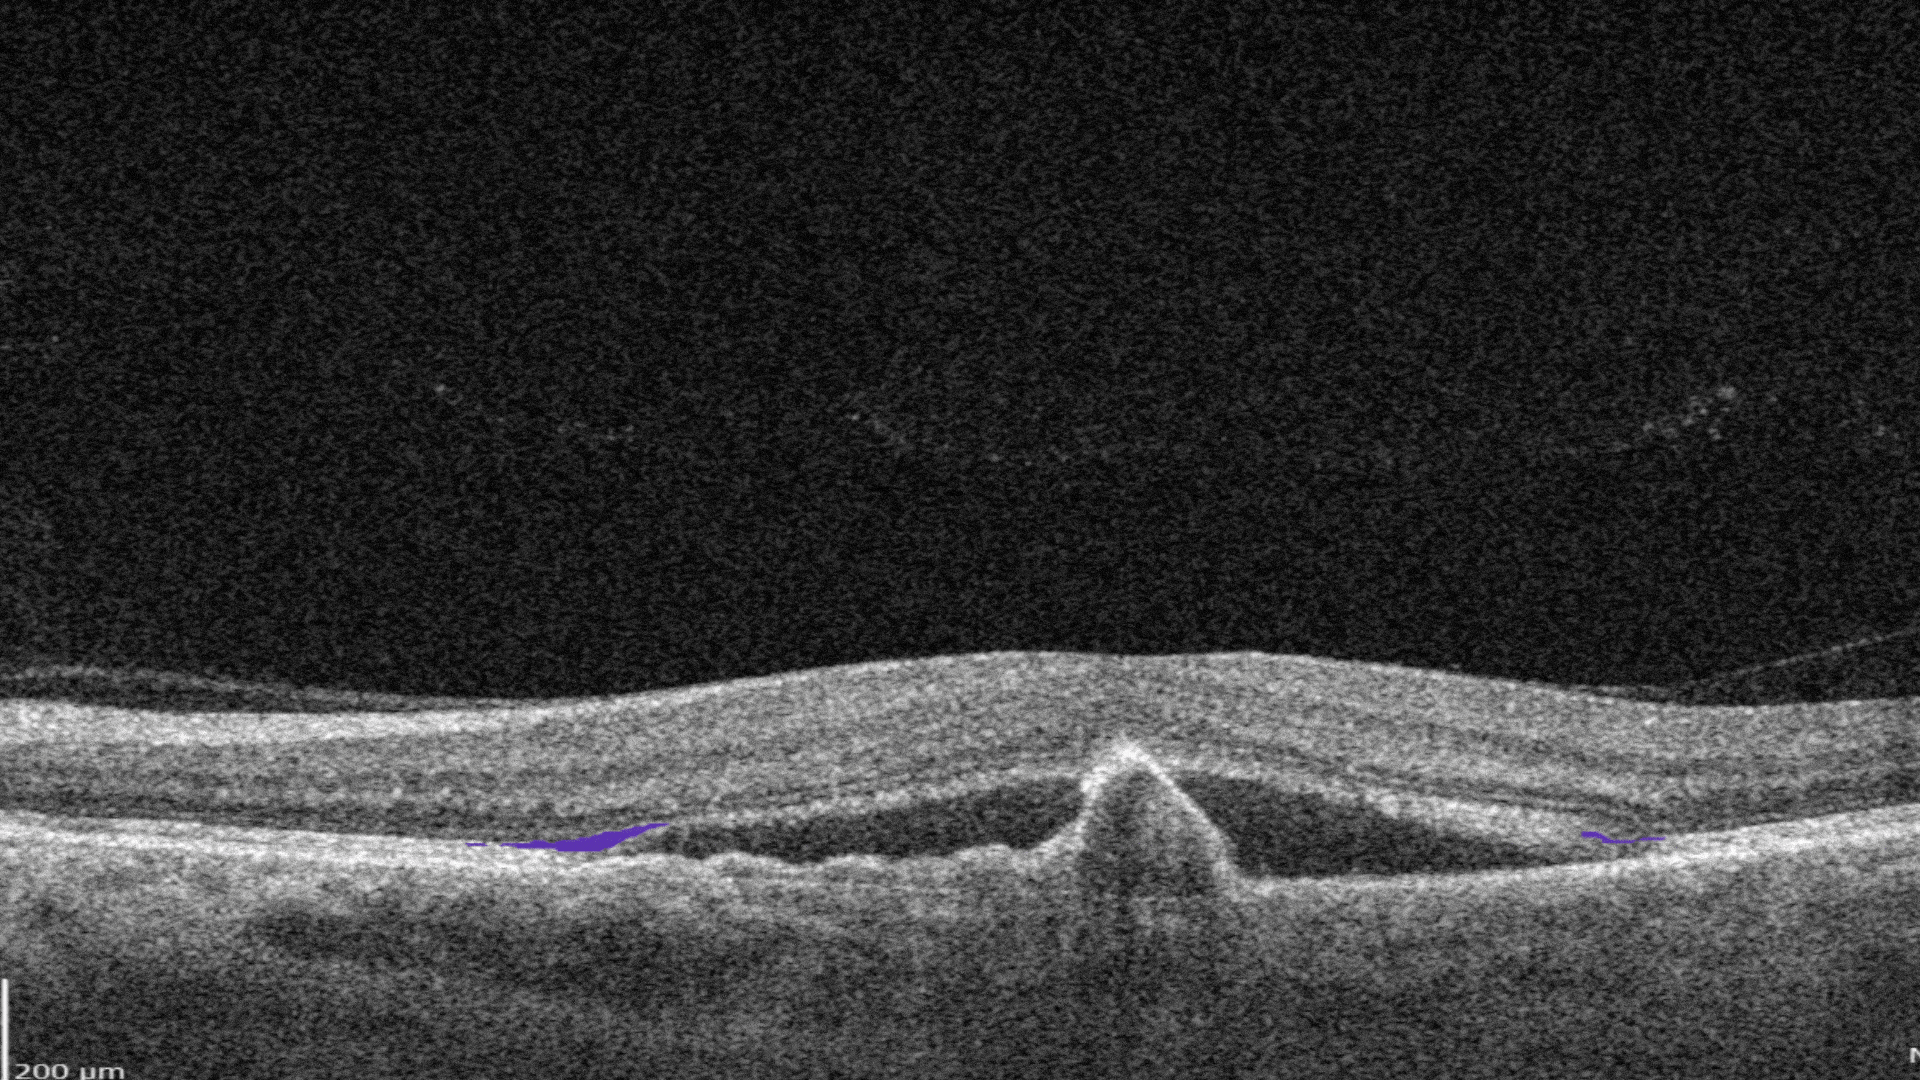

RPE Disruption is the disruption of the Retinal Pigment Epithelium layer

-

Subretinal fluid corresponds to the accumulation of a clear or lipid-rich exudate (serous fluid) in the subretinal space, i.e., between the neurosensory retina (NSR) and the underlying retinal pigment epithelium (RPE), in the absence of retinal breaks, tears, or traction

Fibrovascular RPE detachment. Delamination of the pigment epithelium of the retina is caused by the presence of newly formed vessels (fibrovascular membrane) under the RPE.

Subretinal hyperreflective material (SHRM). It’s a hyperreflective material that is external to the retina and internal to the retinal pigment epithelium (RPE)